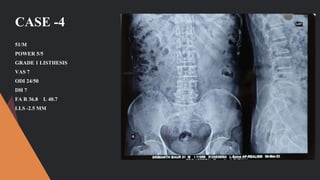

CASE -4

51/M

POWER 5/5

GRADE 1 LISTHESIS

VAS 7

ODI 24/50

DH 7

FA R 36.8 L 40.7

LLS -2.5 MM

ODI 12/50

VAS 3

DH 6 MM

FA R 34.2 L-38.6

NO LISTHESIS

CASE -4 51/M POWER 5/5 GRADE1 LISTHESIS VAS 7 ODI 24/50 DH 7 FA R 36.8 L 40.7 LLS -2.5 MM

POWER 5/5 ODI 12/50 VAS3 DH 6 MM FA R 34.2 L-38.6 NO LISTHESIS